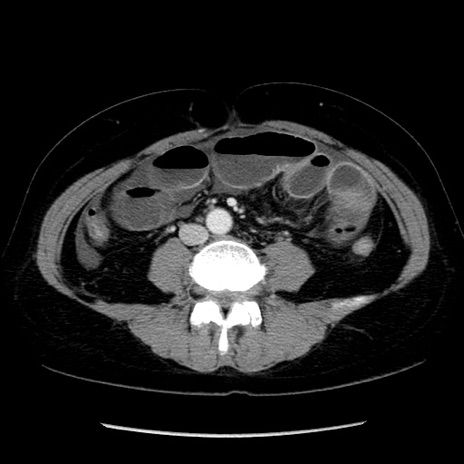

冠状断像